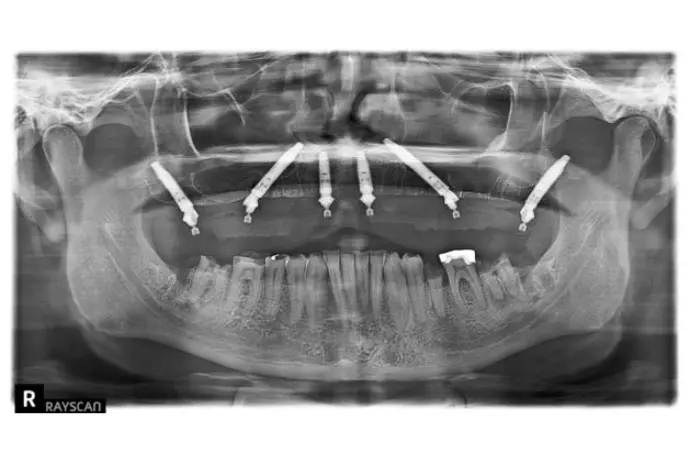

Référentiel Full Arch Club : All-on-4, All-on-X, palatal approach, trans-sinus, pterygoïdes, subpériostés personnalisés. Moins invasif, plus sûr.

Chirurgie et mise en charge immédiate avec une approche sans greffes osseuse et prédictible.

Opération chirurgicale en direct réalisée par le Dr Bernardo Nunes de Sousa